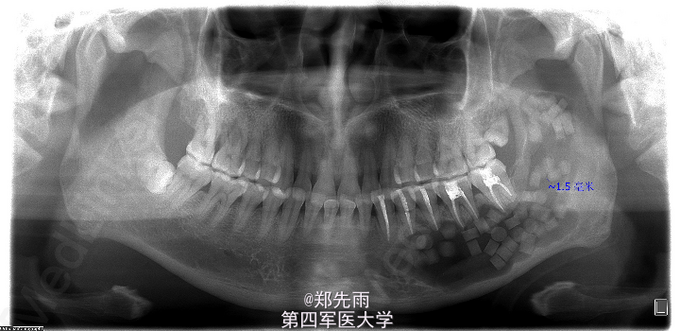

左侧下颌骨角化囊性瘤保守治疗

左侧下颌骨区肿胀不适伴张口受限1月余,外院拍片提示左侧下颌体部及升支部囊性病变,遂来我院

张口度2横指,左侧下颌角部肿胀明显,颊舌侧未及明显膨隆,左下唇无麻木。

诊断:左侧下颌囊性病变,考虑角化囊性瘤及成釉细胞瘤。 处理:行术前累积牙根管治疗,术中行刮治术+术中冰冻,提示角化囊性瘤,予以医用硫酸钙充填囊腔。